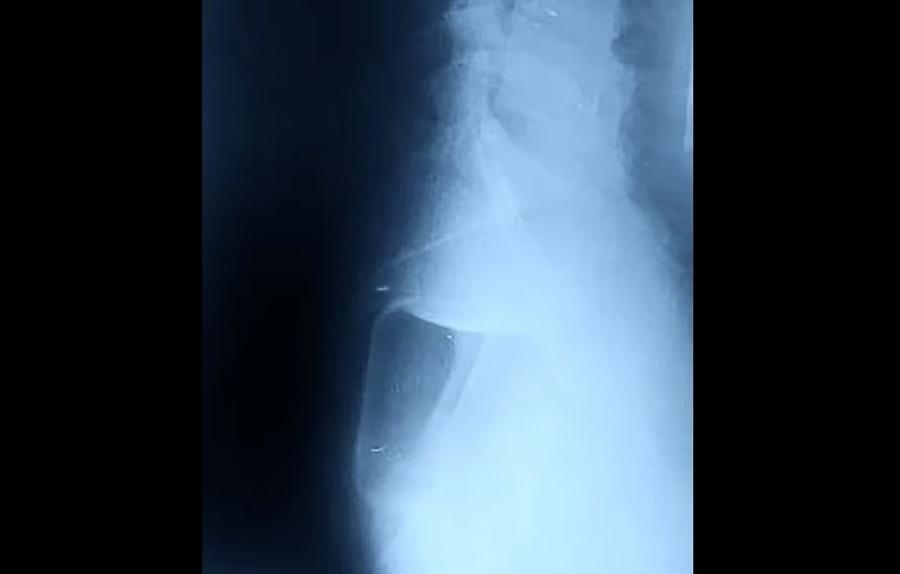

俄羅斯一名男子將500毫升的玻璃瓶塞進肛門。(互聯網)

從報道顯示的X光片看見,體積不細的玻璃瓶在肛門內較高位置,醫生最後成功取出它,連帶一個安全套。報道稱,那男子將一個容量500毫升的玻璃瓶塞進肛門,並將其推進腸道,最後因無法取出而求醫。俄羅斯下諾夫哥羅德一間醫院公開有關個案,稱醫生非道德警察,不會評論病人非傳統的性傾向,呼籲民眾若遇相同情況,須尋求醫療協助。